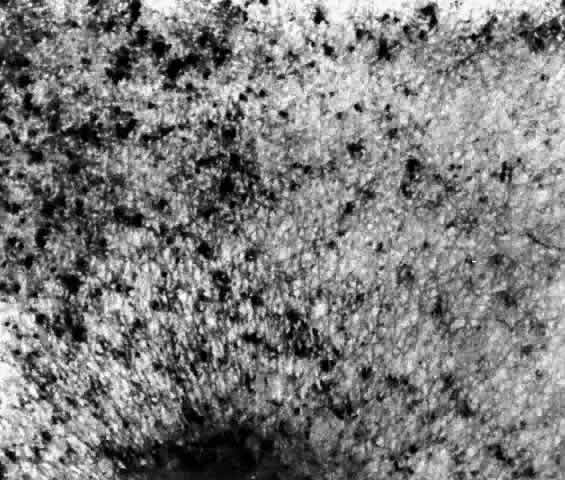

These deposits are strongly birefringent, and striking macular birefringence may be readily visualized in sections of the retina (Fig. 5) even in the unstained state as well as when lightly stained with cresyl violet or sudanophilic dyes.8 Loss of the ganglion cells and atrophy of the optic nerve, which is also evident, are accompanied by a thinning of the nerve fiber layer.

Fig. 5. Birefringence of ganglion cell layer of macula in Tay-Sachs disease. Frozen section, cresyl violet stain, photographed between crossed polaroids (x 80). (Cogan DG, Kuwabara T: The sphingolipidoses and the eye. Arch Ophthalmol 79:437, 1968. Copyright © 1968, American Medical Association)

Histochemical stains have characterized the retinal lipid as a glycolipid,7 and lipid chromatography of retinal cells shows a prominent spot of GM2-ganglioside.9